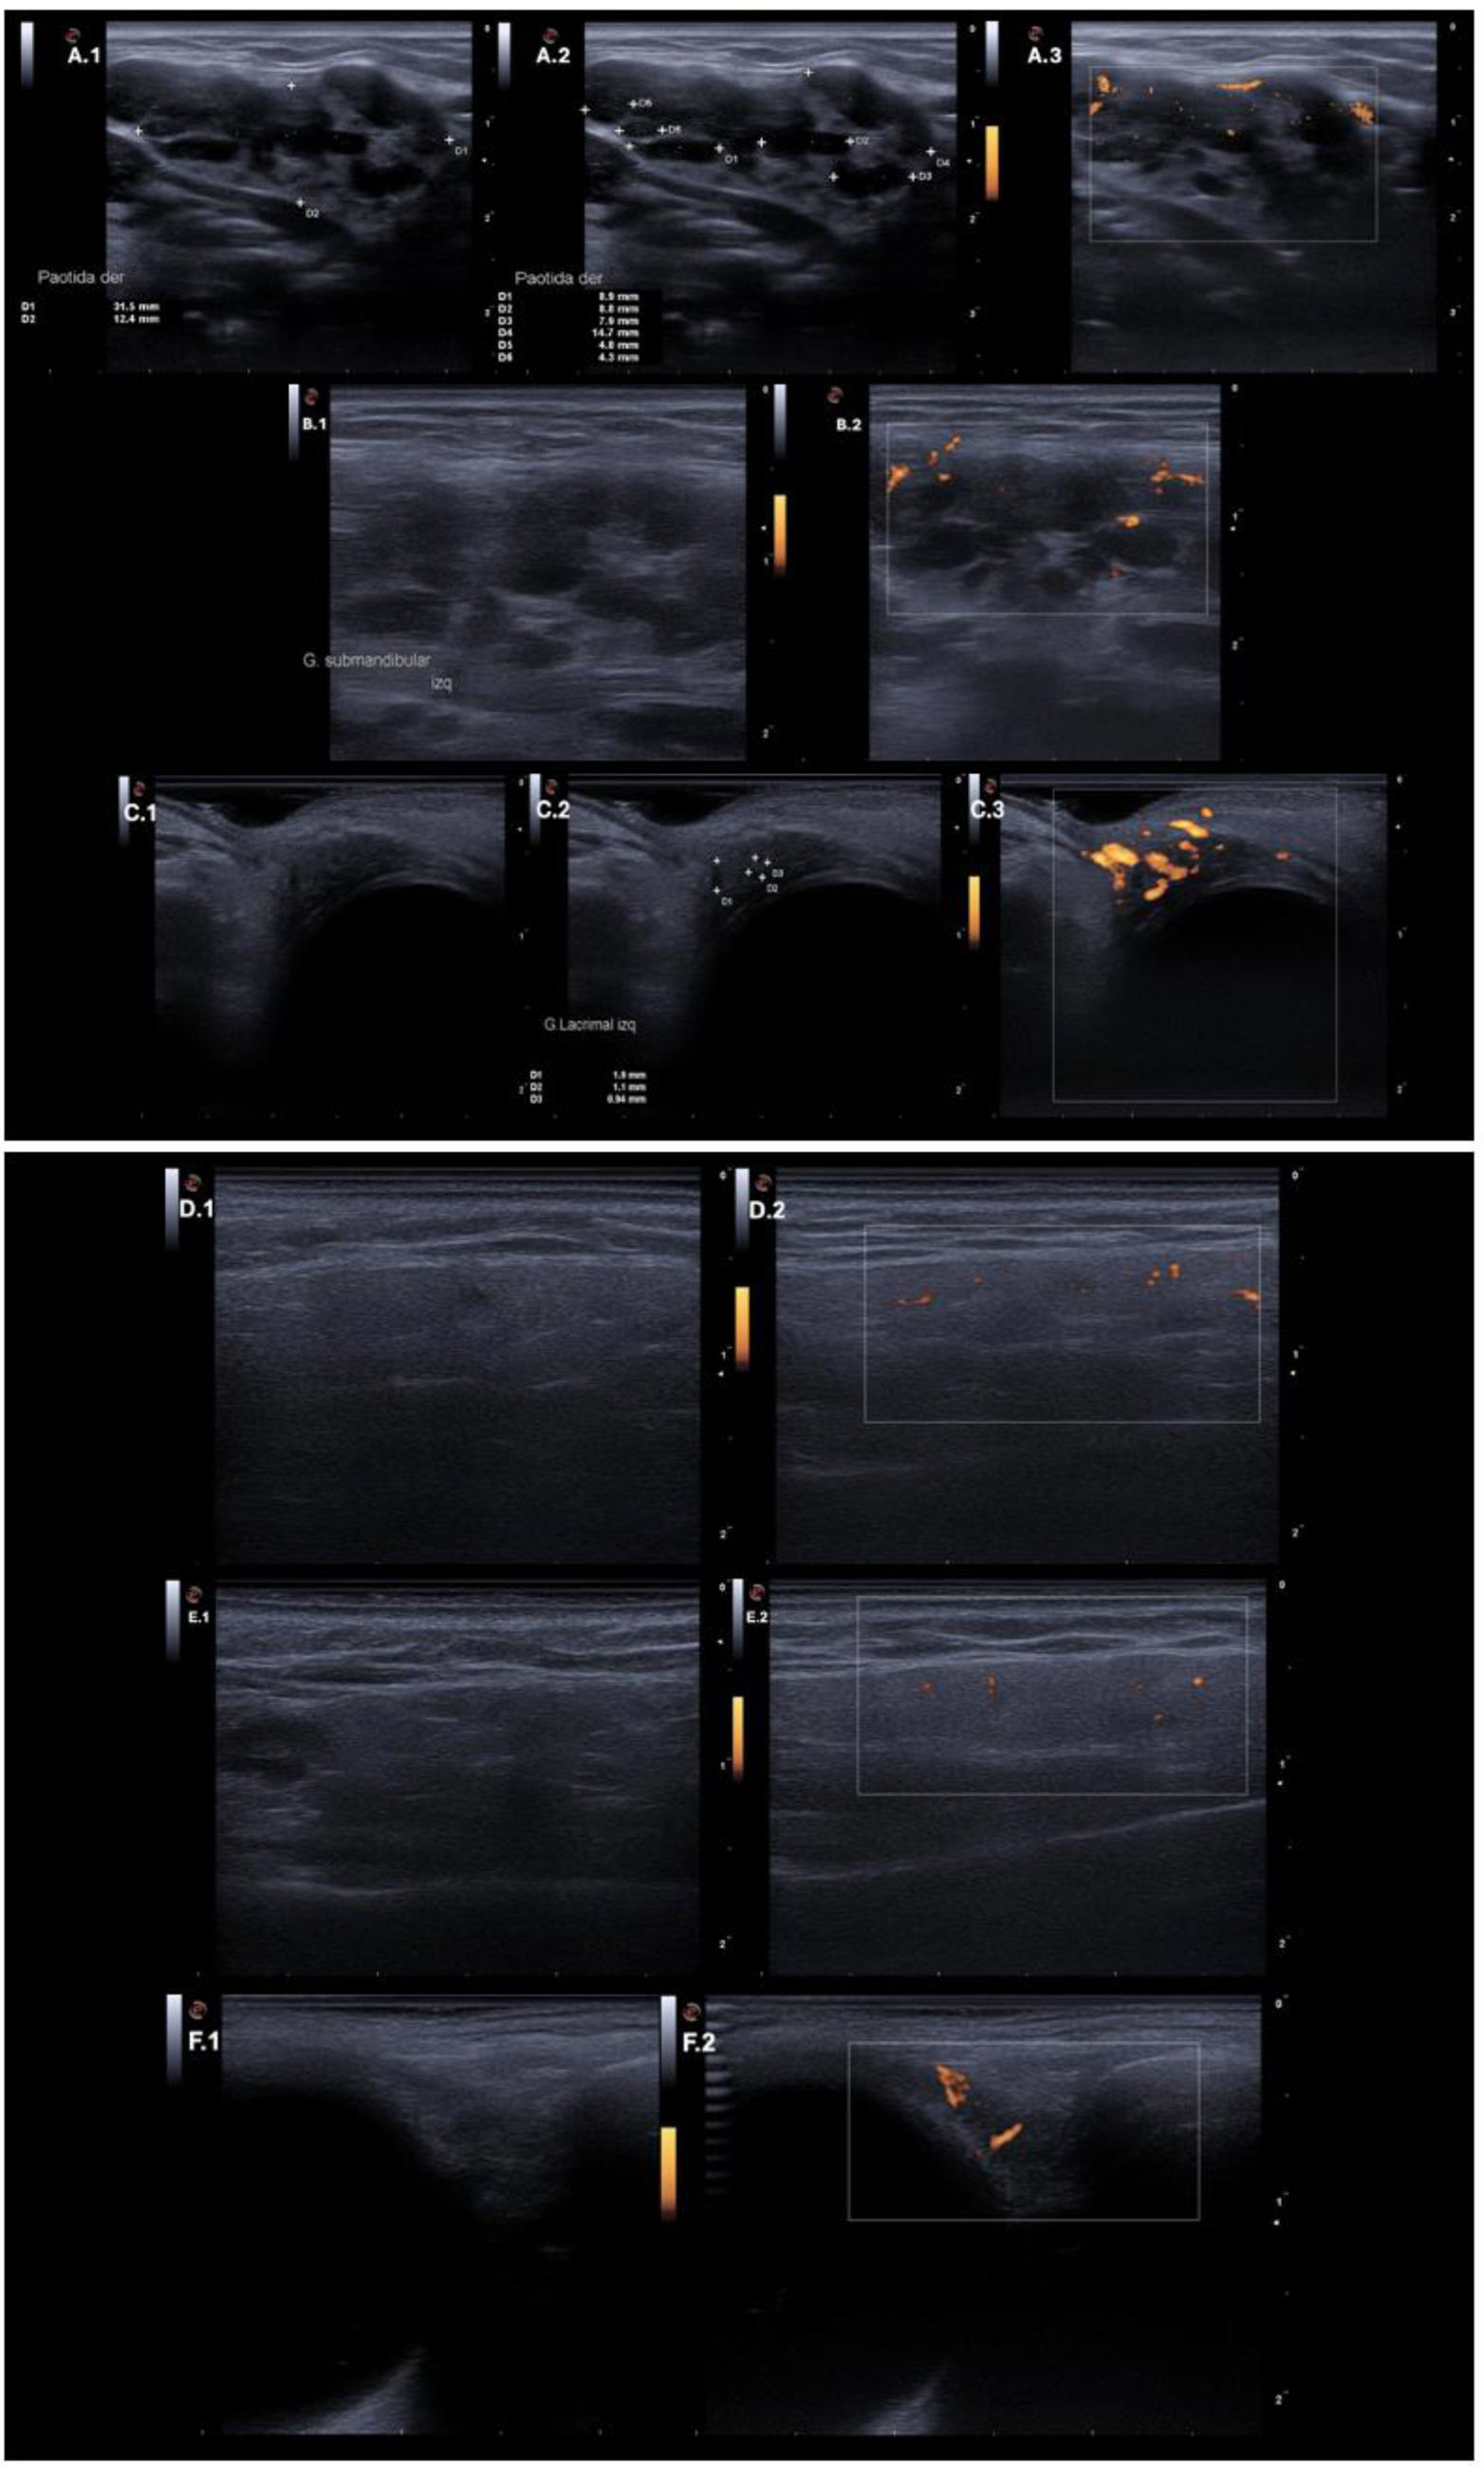

With a clinical suspicion of IgG4-RD, an ultrasound evaluation was performed using an ESAOTE ultrasound system with a high-frequency IHX 6-25 linear transducer (3–22MHz), gain settings of 50–80%, and a depth of 1–2cm. Power Doppler analysis of the salivary glands was conducted following the scoring system proposed by Zhou et al. (Table 1), yielding a total score of 32 points. Ultrasound assessment of the lacrimal glands revealed parenchymal heterogeneity, the presence of hypoechoic areas, and positive power Doppler findings, further supporting the diagnostic suspicion (Fig. 2). These findings suggested the diagnosis of IgG4-RD but warranted confirmatory studies and further evaluation to rule out differential diagnoses (Table 2), these evaluations ruled out infectious and oncologic diseases, as well as Sjögren's syndrome and sarcoidosis.

Ultrasound findings of salivary and lacrimal glands. Ultrasound findings of the salivary and lacrimal glands in the initial assessment and after pharmacological management. Panel (A) Right parotid gland. Evident heterogeneity in A.1. Anechoic patchy areas between 6mm and <15mm in A.2. Positive Doppler signal in A.3. Panel (B) Left submandibular gland. Evident heterogeneity and anechoic patchy areas between 6mm and <15mm in B.1. Positive Doppler signal in B.2. Panel (C) Left lacrimal gland. Evident heterogeneity in C.1. Anechoic patchy areas <6mm in C.2. Abundant Doppler signal in C.3. Panel (D) Right parotid gland after treatment. Parenchymal echogenicity similar to the thyroid in D.1. Mildly positive Doppler signal in D.2. Panel (E) Left submandibular gland after treatment. Parenchymal echogenicity similar to the thyroid, minimal heterogeneity with a hypoechoic area between 6 and 15mm in E.1. Mildly positive Doppler signal in E.2. Panel (F) Left lacrimal gland after treatment. Parenchymal echogenicity similar to the thyroid in F.1. Mildly positive Doppler signal in F.2.

The patient tolerated steroid dose reduction. Within the first 15 days, a decrease in the size of the lacrimal and parotid glands was observed, along with improved parenchymal echogenicity, resembling that of the thyroid gland. There was a reduced proportion of hypoechoic areas compared to the initial evaluation, with patchy regions measuring less than 6mm (previously 6–15mm). Additionally, a decrease in power Doppler signal intensity was noted (see Table 1 and Fig. 2). The follow-up Zhou score was recorded at 11, remaining within the classificatory range but showing a significant reduction compared to the initial assessment. The lacrimal glands demonstrated a marked decrease in size, along with a substantial reduction in power Doppler findings. At 30 days after the last Rituximab infusion, a pronounced reduction in the size of the lacrimal and salivary glands was documented (Fig. 2), as well as improvement in the ureteral lesion. The patient continued treatment with prednisolone 5mg, methotrexate, and completed the Rituximab infusion regimen.

In this patient, parotid heterogeneity was observed with patchy anechoic areas measuring between 6mm and <15mm, along with a strongly positive power Doppler signal. Similar findings were noted in the submandibular and lacrimal glands. These abnormalities could serve as early indicators of disease, enhance diagnostic accuracy, and influence disease progression through early treatment initiation. Although lacrimal glands are not currently included in this scoring system, we documented similar alterations in this case, suggesting that future refinements to the scoring criteria may improve the diagnostic performance of ultrasonography in IgG4-RD. However, the external validity of such diagnostic strategies remains to be established.